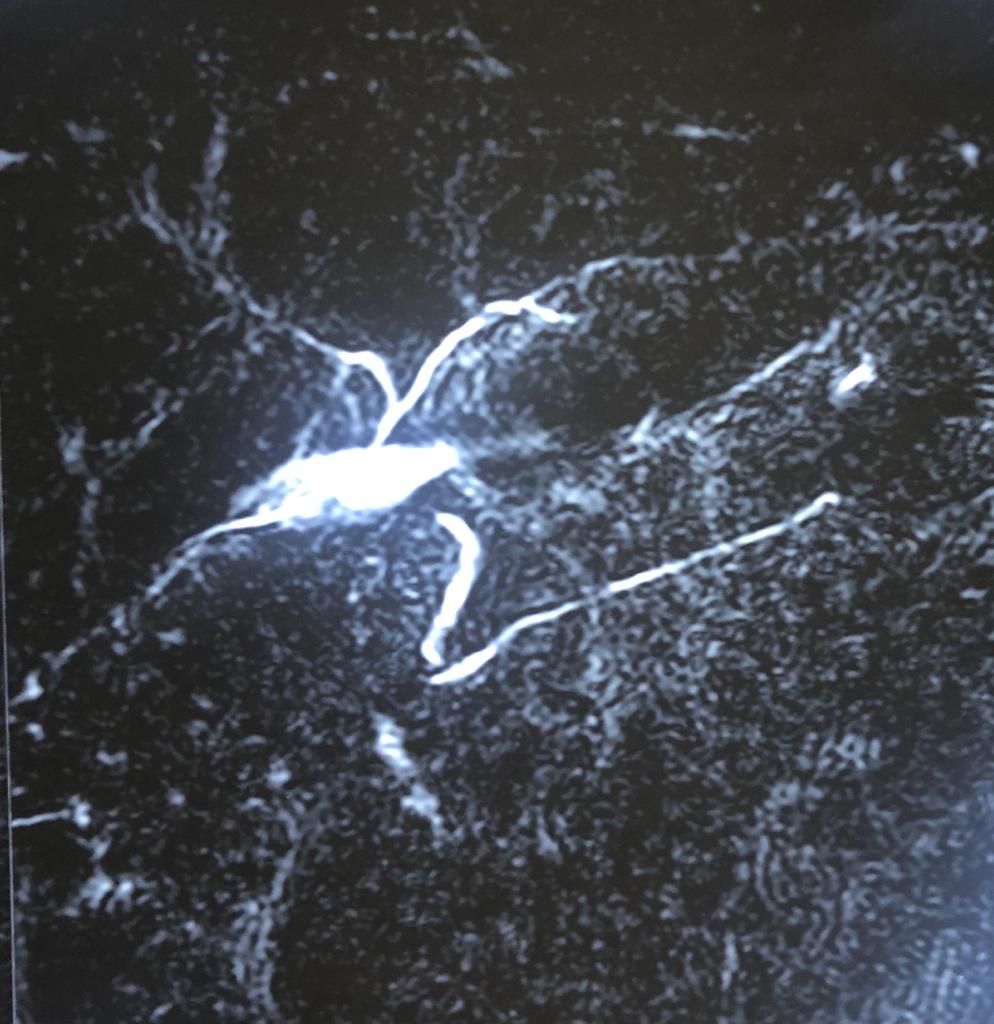

A Challenging Scenario: 40-year-old male with idiopathic chronic pancreatitis with intractable pain and sitophobia

40 year old male with idiopathic chronic pancreatitis presented with intractable pain, sitophobia with severe weight loss (adult male weighs 29 Kg) and history of recurrent episodes of GI bleed. He also has CKD (cr1.7) related to neurogenic bladder. Patient was shifted to us in shock with HB 3 gm % and massive GI bleed. MRI and CT angio showed a large 6x5 cm Pseudoaneurysm in uncinate process of pancreas probably arising from inferior pancreaticoduordenal artery causing hemosuccus pancreas. In view of CKD we chose to tackle aneurysm by direct glue embolisation of aneurysm sac to avoid the high volume contrast of conventional angio (image) Pt was put on NJ feeds in view of severe malnutrition secondary to intractable pain and sitophobia. Post embolisation 2 months later he came back with weight gain of 8 kg and a stable Hb%. His Repeated CT scan showed a persistent intrapancreatic head cyst with dilated pd in body and tail. The aneurysm cavity filled with glue cast has shrunk to almost one fifth the initial size. In view of large duct disease with Pseudoaneurysm we decided to go ahead with a whipple pancreaticoduodenectomy. The post op specimen shows the intrapancreatic cyst and the glue cast of the aneurysm (yellow arrow). His recovery was uneventful and is completely pain free post procedure.